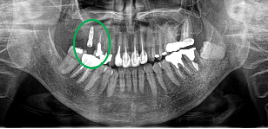

Before

※赤丸は、歯根が破折していたため抜歯しました

※黄色丸は、2006年10月に埋入したインプラント

After

※緑丸は、今回埋入したインプラント